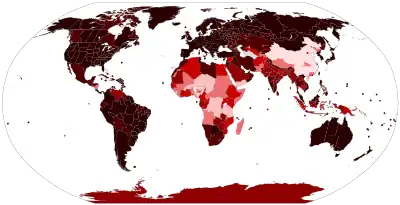

Confirmed deaths per 100,000 population

as of 20 December 2023 | |||||||

| Confirmed cases | 712,626,736[3] | ||||||

Deaths | 6,202,362[3] (reported) 18.2–33.5 million[4] (estimated) | ||||||

| Fatality rate | 1.02%[5] | ||||||

The COVID-19 pandemic, also known as the coronavirus pandemic, is a global pandemic of coronavirus disease 2019 (COVID-19) caused by severe acute respiratory syndrome coronavirus 2 (SARS-CoV-2). The novel virus was first identified in an outbreak in the Chinese city of Wuhan in December 2019, and spread to other areas of Asia and then worldwide in early 2020. The World Health Organization (WHO) declared the outbreak a public health emergency of international concern (PHEIC) on 30 January 2020. The WHO ended its PHEIC declaration on 5 May 2023. As of 17 January 2024, the pandemic has caused 712,626,736[3] cases and 6,202,362[3] confirmed deaths, ranking it fifth in the list of the deadliest epidemics and pandemics in history.

As of 10 March 2023, more than 6.88 million[5] deaths had been attributed to COVID-19. The first confirmed death was in Wuhan on 9 January 2020.[62] These numbers vary by region and over time, influenced by testing volume, healthcare system quality, treatment options, government response,[63] time since the initial outbreak, and population characteristics, such as age, sex, and overall health.[64]

Multiple measures are used to quantify mortality.[65] Official death counts typically include people who died after testing positive. Such counts exclude deaths without a test.[66] Conversely, deaths of people who died from underlying conditions following a positive test may be included.[67] Countries such as Belgium include deaths from suspected cases, including those without a test, thereby increasing counts.[68]

Official death counts have been claimed to underreport the actual death toll, because excess mortality (the number of deaths in a period compared to a long-term average) data show an increase in deaths that is not explained by COVID-19 deaths alone.[69] Using such data, estimates of the true number of deaths from COVID-19 worldwide have included a range from 18.2 to 33.5 million (≈27.4 million) by 18 November 2023 by The Economist,[4][69] as well as over 18.5 million by 1 April 2023 by the Institute for Health Metrics and Evaluation[70] and ≈18.2 million (earlier) deaths between 1 January 2020, and 31 December 2021, by a comprehensive international study.[71] Such deaths include deaths due to healthcare capacity constraints and priorities, as well as reluctance to seek care (to avoid possible infection).[72] Further research may help distinguish the proportions directly caused by COVID-19 from those caused by indirect consequences of the pandemic.[71]

In May 2022, the WHO estimated the number of excess deaths by the end of 2021 to be 14.9 million compared to 5.4 million reported COVID-19 deaths, with the majority of the unreported 9.5 million deaths believed to be direct deaths due the virus, rather than indirect deaths. Some deaths were because people with other conditions could not access medical services.[73][74]

A December 2022 WHO study estimated excess deaths from the pandemic during 2020 and 2021, again concluding ≈14.8 million excess early deaths occurred, reaffirming and detailing their prior calculations from May as well as updating them, addressing criticisms. These numbers do not include measures like years of potential life lost and may make the pandemic 2021's leading cause of death.[75][76][61]